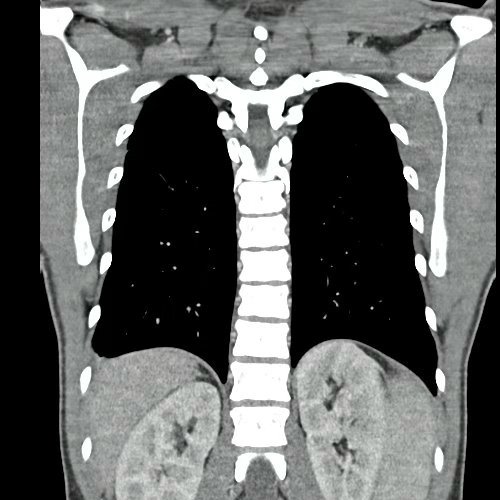

• TAC de Tórax (23/10/24): Escaso derrame pleural bilateral. No se visualiza imagen sugerente de Neumopatía.

TAC de tórax corte coronal y axial previas (23/10/24)